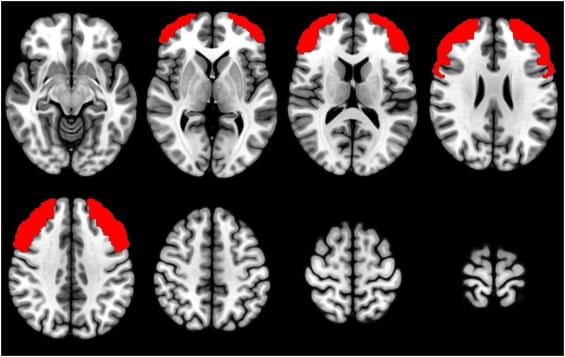

Our recent study, published in Psychiatry Research: Neuroimaging, set out to explore whether cognitive testing and brain imaging could help distinguish NMDAR encephalitis from schizophrenia (Kelleher et al, 2025). We compared three groups: Patients who had been diagnosed with and treated for NMDAR encephalitis, individuals with schizophrenia, and healthy controls. In addition to a comprehensive battery of cognitive tests, participants completed the N-back task—a computer-based task that measures short-term memory and attention—while undergoing fMRI brain scanning.

Previous meta-analyses (e.g., Glahn et al., 2005) have shown that schizophrenia is associated with reduced activation in the dorsolateral prefrontal cortex during the N-back task. However, to our knowledge, this is the first study to directly compare neural activation during this task in patients with NMDAR encephalitis with patients with schizophrenia and healthy controls.

Our findings were encouraging. Although patients with NMDAR encephalitis showed a trend toward slightly lower performance in several cognitive domains compared with healthy controls, and a trend toward higher performance in these same domains compared with patients with schizophrenia, none of the differences reached statistical significance. This suggests that, over time, cognitive function in individuals with NMDAR encephalitis may return to near-normal levels, particularly when early and effective treatment is administered.